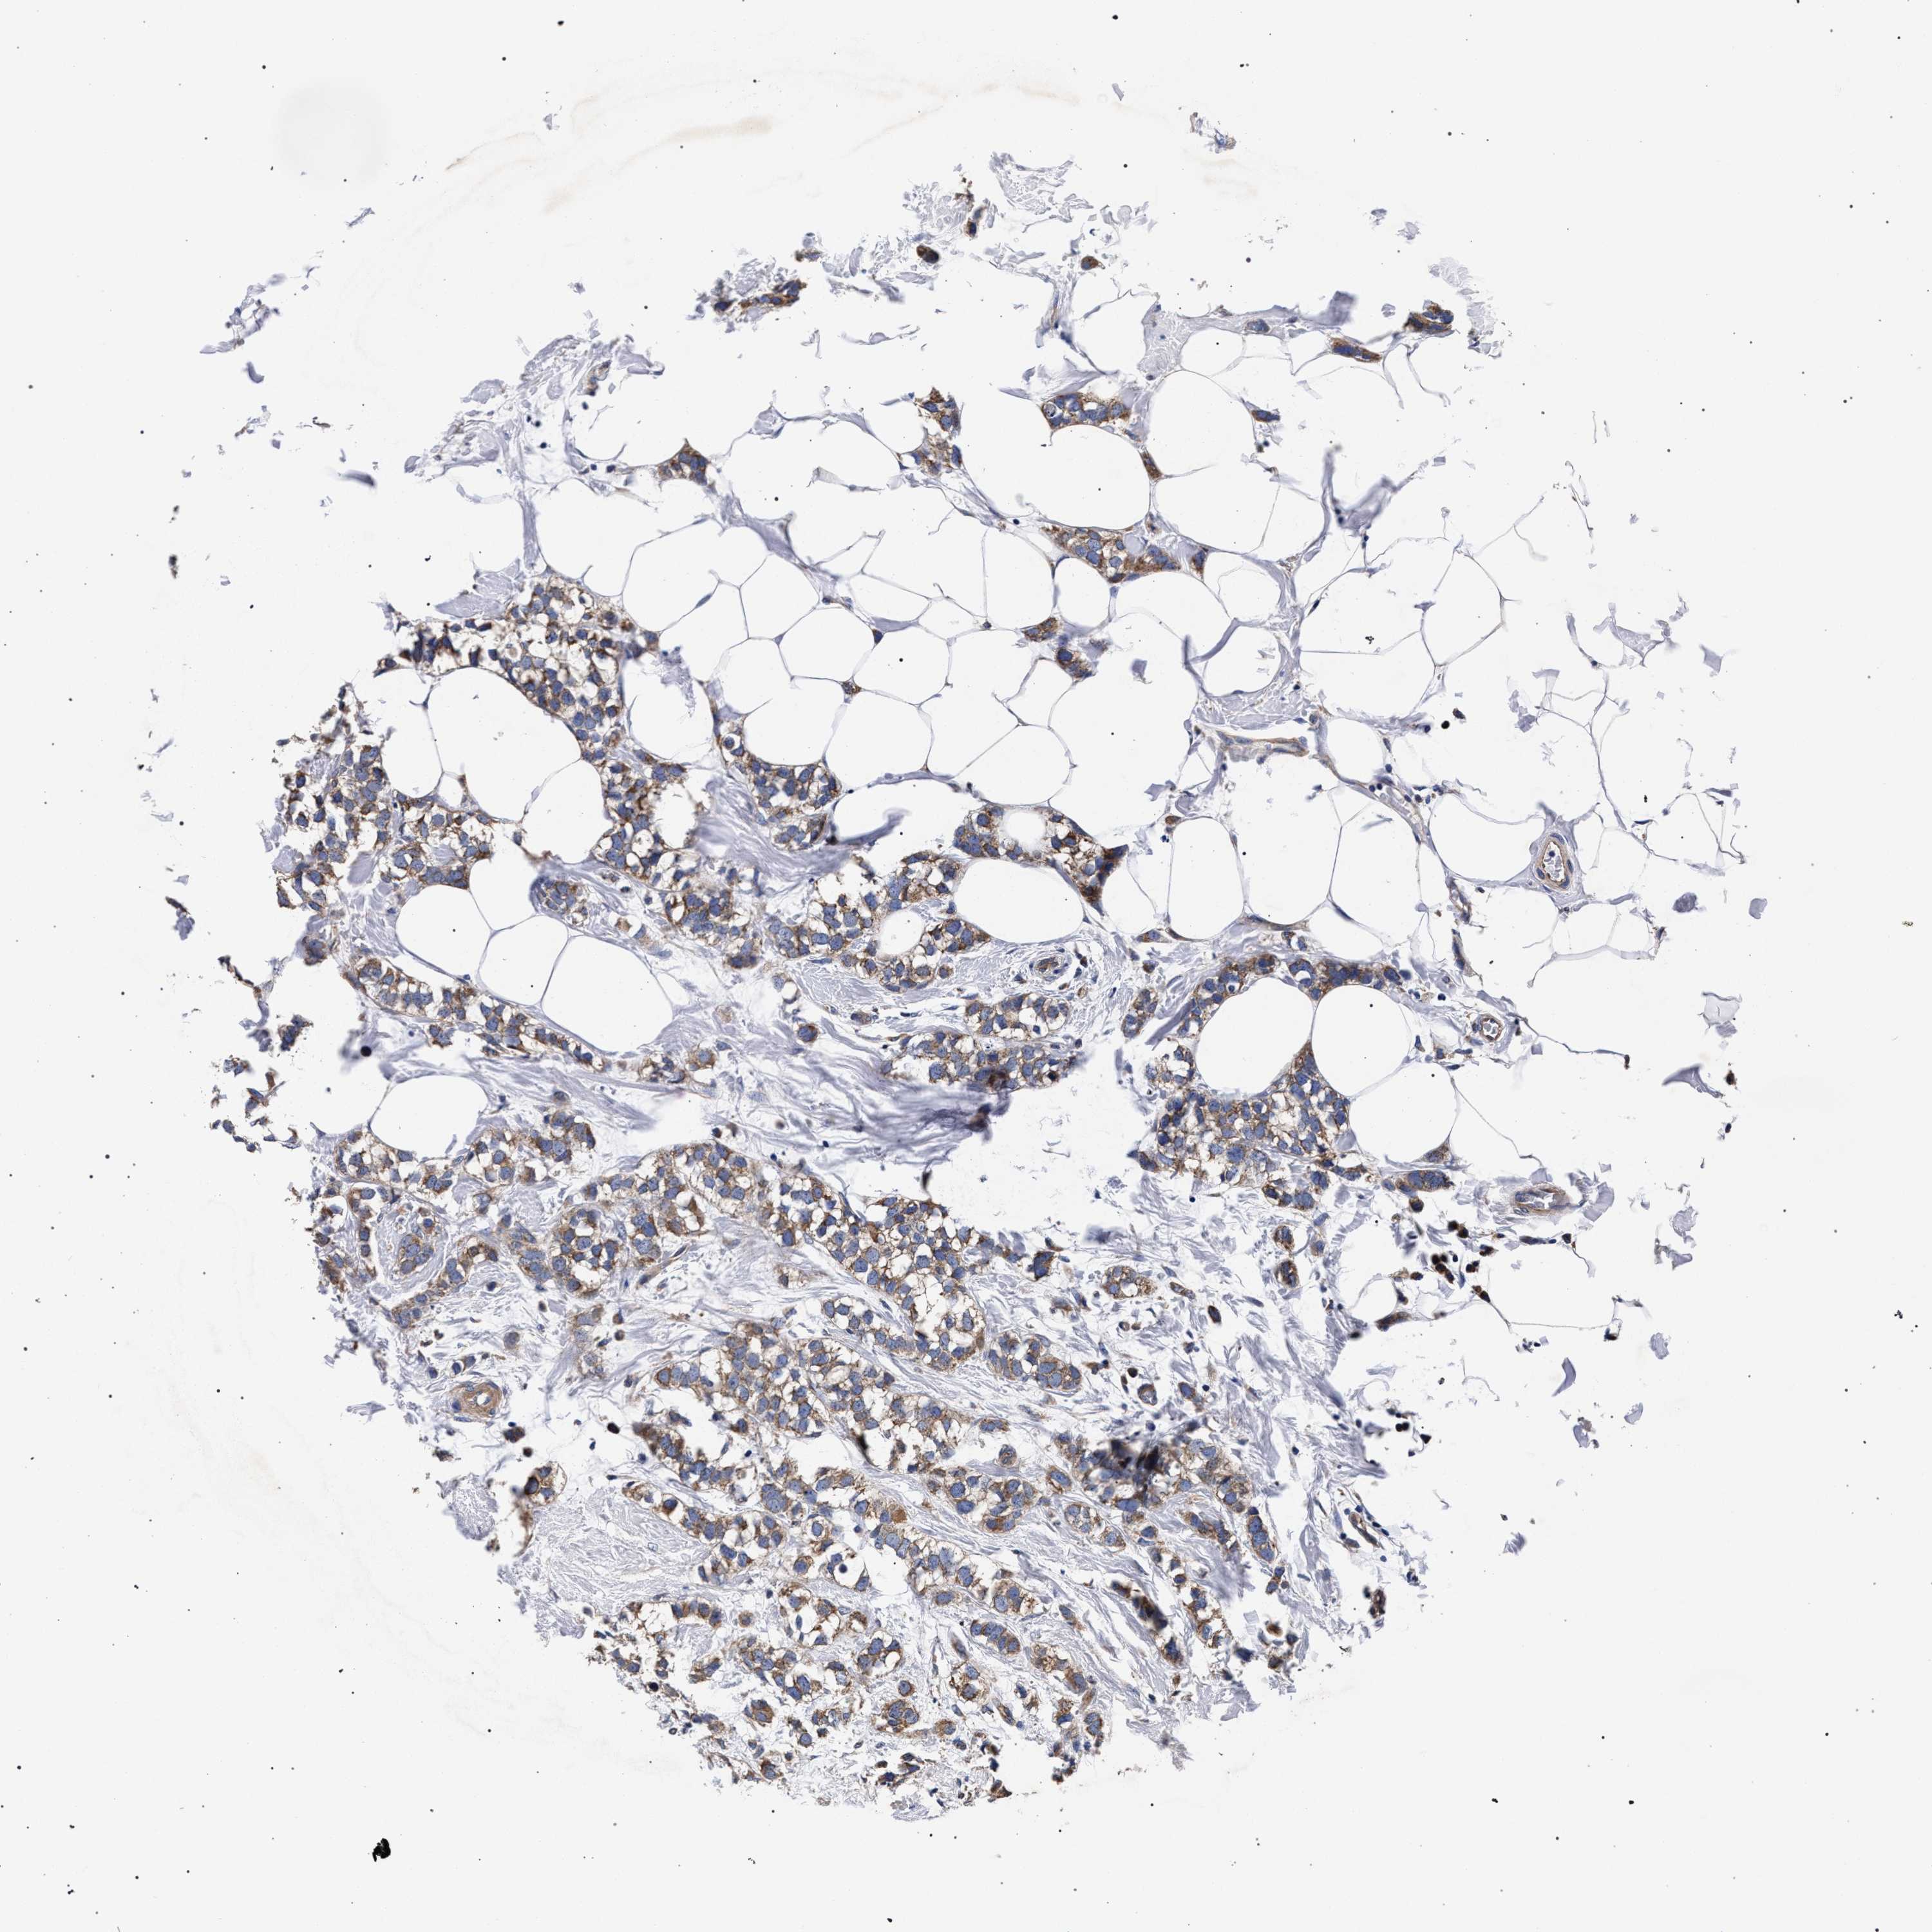

CANCER BREAST CANCER Show tissue menu

BRCA TCGA BRCA VALIDATION PROTEIN EXPRESSION